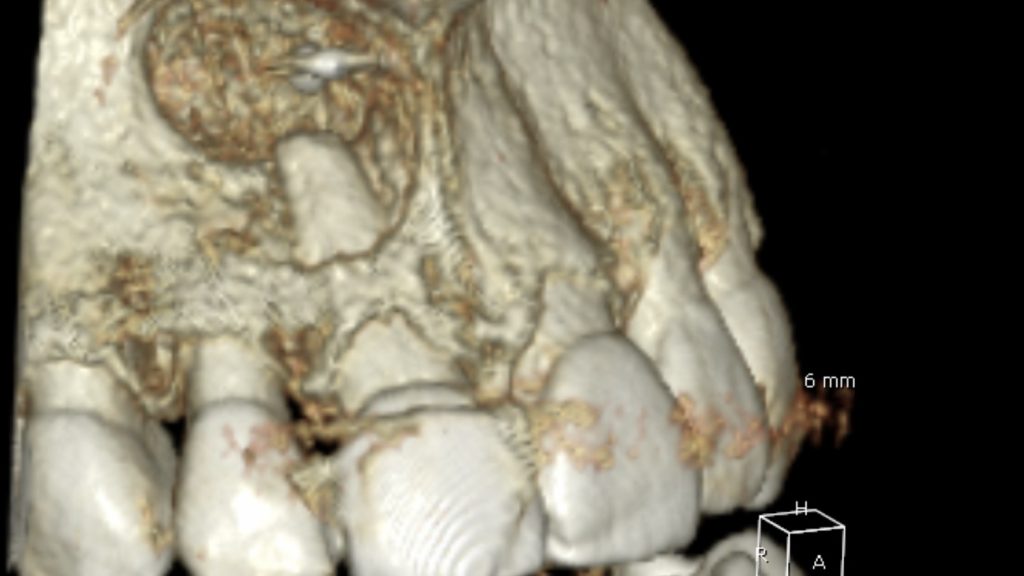

Surgical stage